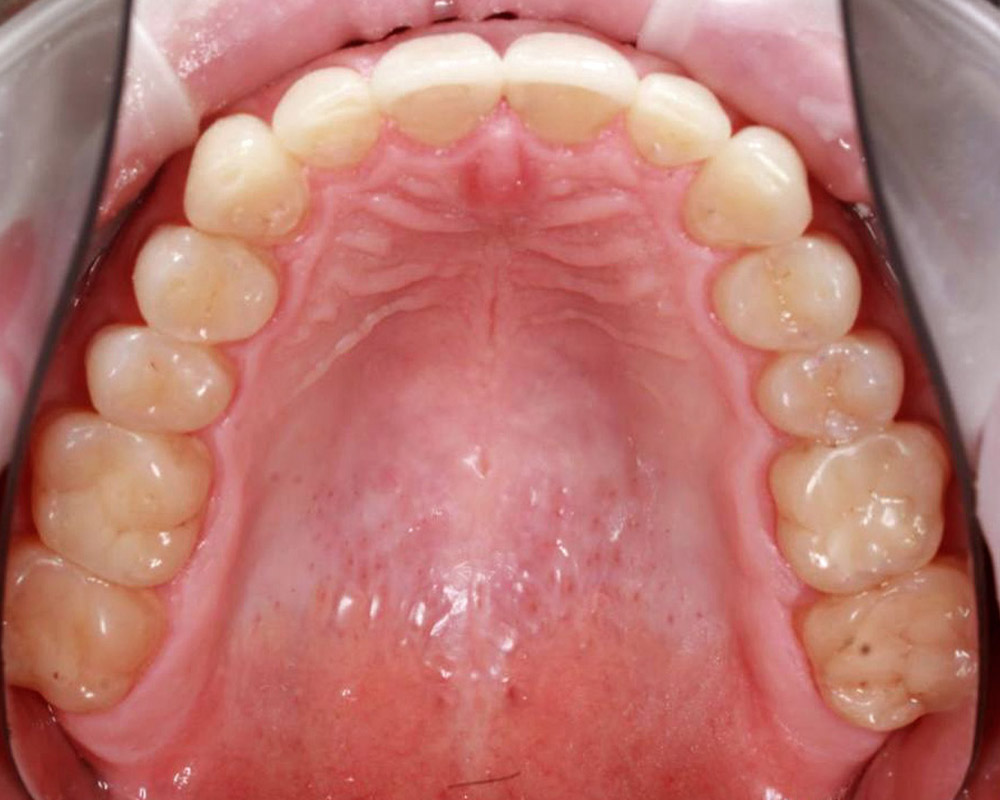

Кейс 12

Бирковская Екатерина Александровна

Количество кап ВЧ 24

Количество кап НЧ 41

ДО

ПОСЛЕ